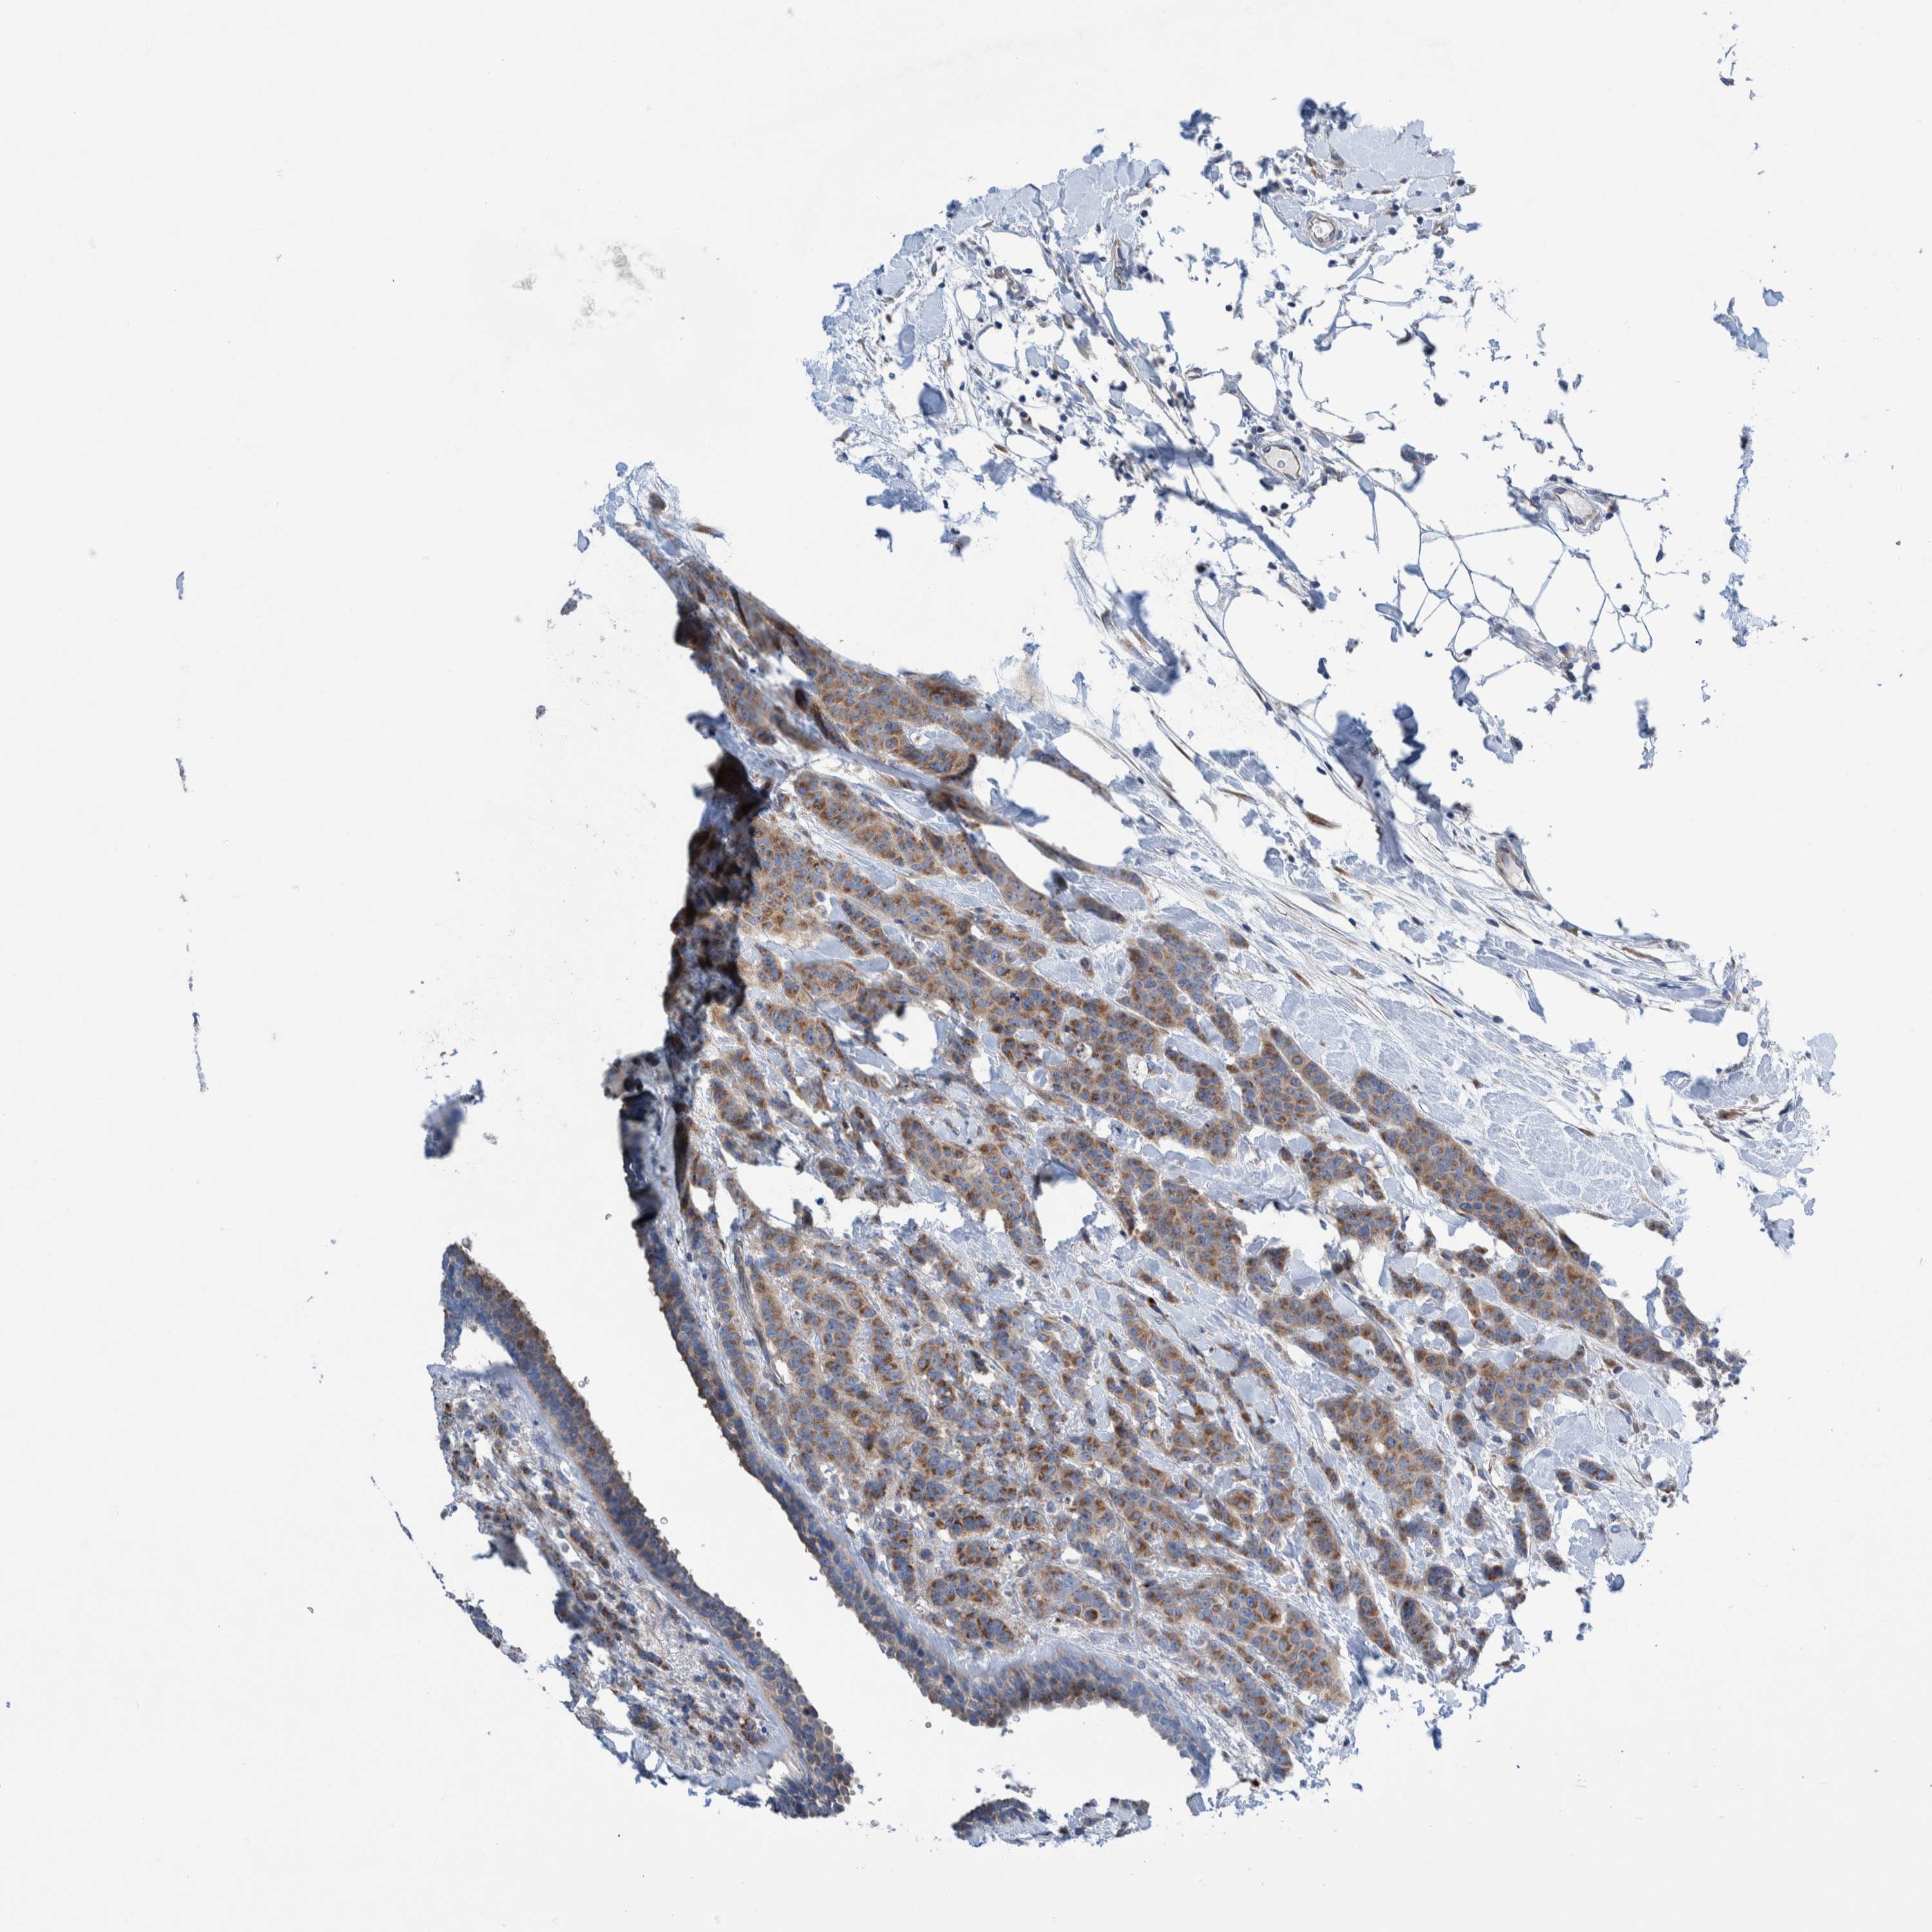

CANCER BREAST CANCER Show tissue menu

BRCA TCGA BRCA VALIDATION PROTEIN EXPRESSION

ANTIBODIES

AND

VALIDATION